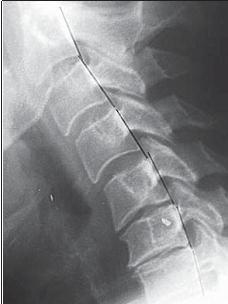

При таких патологических процессах фиброзное кольцо растрескивается более интенсивно именно в зонах «хрящевой метаплазии», что в дальнейшем приводит к развитию протрузий или грыж межпозвонковых дисков. Вторичность поражения фиброзного кольца подтверждается тем, что трещины распределяются на кольцо изнутри межпозвонкового диска и степень их распространения пропорциональна выраженности деструкции пульпозного ядра. При сегментарной нестабильности происходят движения в виде чрезмерного сгибания и разгибания, а также несвойственные скольжения позвонков кпереди или кзади. При функциональной рентгенографии это определяется как смещение тела вышележащего позвонка при сгибании несколько кпереди (рентгенограмма № 2), а при разгибании — кзади (рентгенограмма № 3), или изменение равномерной дуги (лордоза) с локальным выпрямлением (или усугублением).

Рентгенограмма № 2